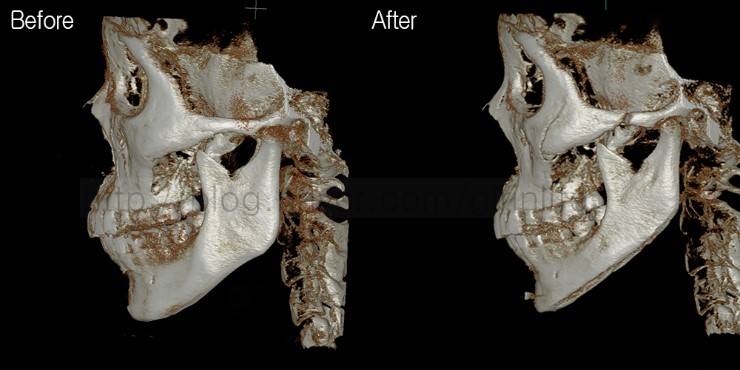

왼쪽입니다. 광대체부는 부분절골해서 안으로 밀어넣고 긴곡선으로 턱라인이 정리되었습니다.

앞턱에 보이는 작은 이물질은 앞턱보형물의 이동을 방지하는 고정장치입니다.

오른쪽입니다. 마찬가지로 광대체부는 부분절골하고 턱라인은 긴곡선절골하였습니다.